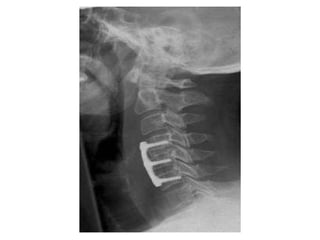

POST OPERATIVE X-RAY

Post operative image The patient had an ACDF at C4/C5 and C5/C6. The kyphosis is corrected and hopefully will be maintained until fusion in the hard collar.  She will wear the collar for 3 months.

Surgery performed was an anterior cervical discectomy and fusion using the patients’ iliac bone.  I decided to fuse at two levels C4/C5 and C5/C6 though the main focus was really to do a good decompression of the space behind the C5/C6 disc, which is the site of maximal compression on the MRI scan.

Surgery performed wasan anterior cervical discectomy and fusion using the patients’ iliac bone. I decided to fuse at two levels C4/C5 and C5/C6 though the main focus was really to do a good decompression of the space behind the C5/C6 disc, which is the site of maximal compression on the MRI scan.

Post operative imageThe patient had an ACDF at C4/C5 and C5/C6. The kyphosis is corrected and hopefully will be maintained until fusion in the hard collar. She will wear the collar for 3 months.